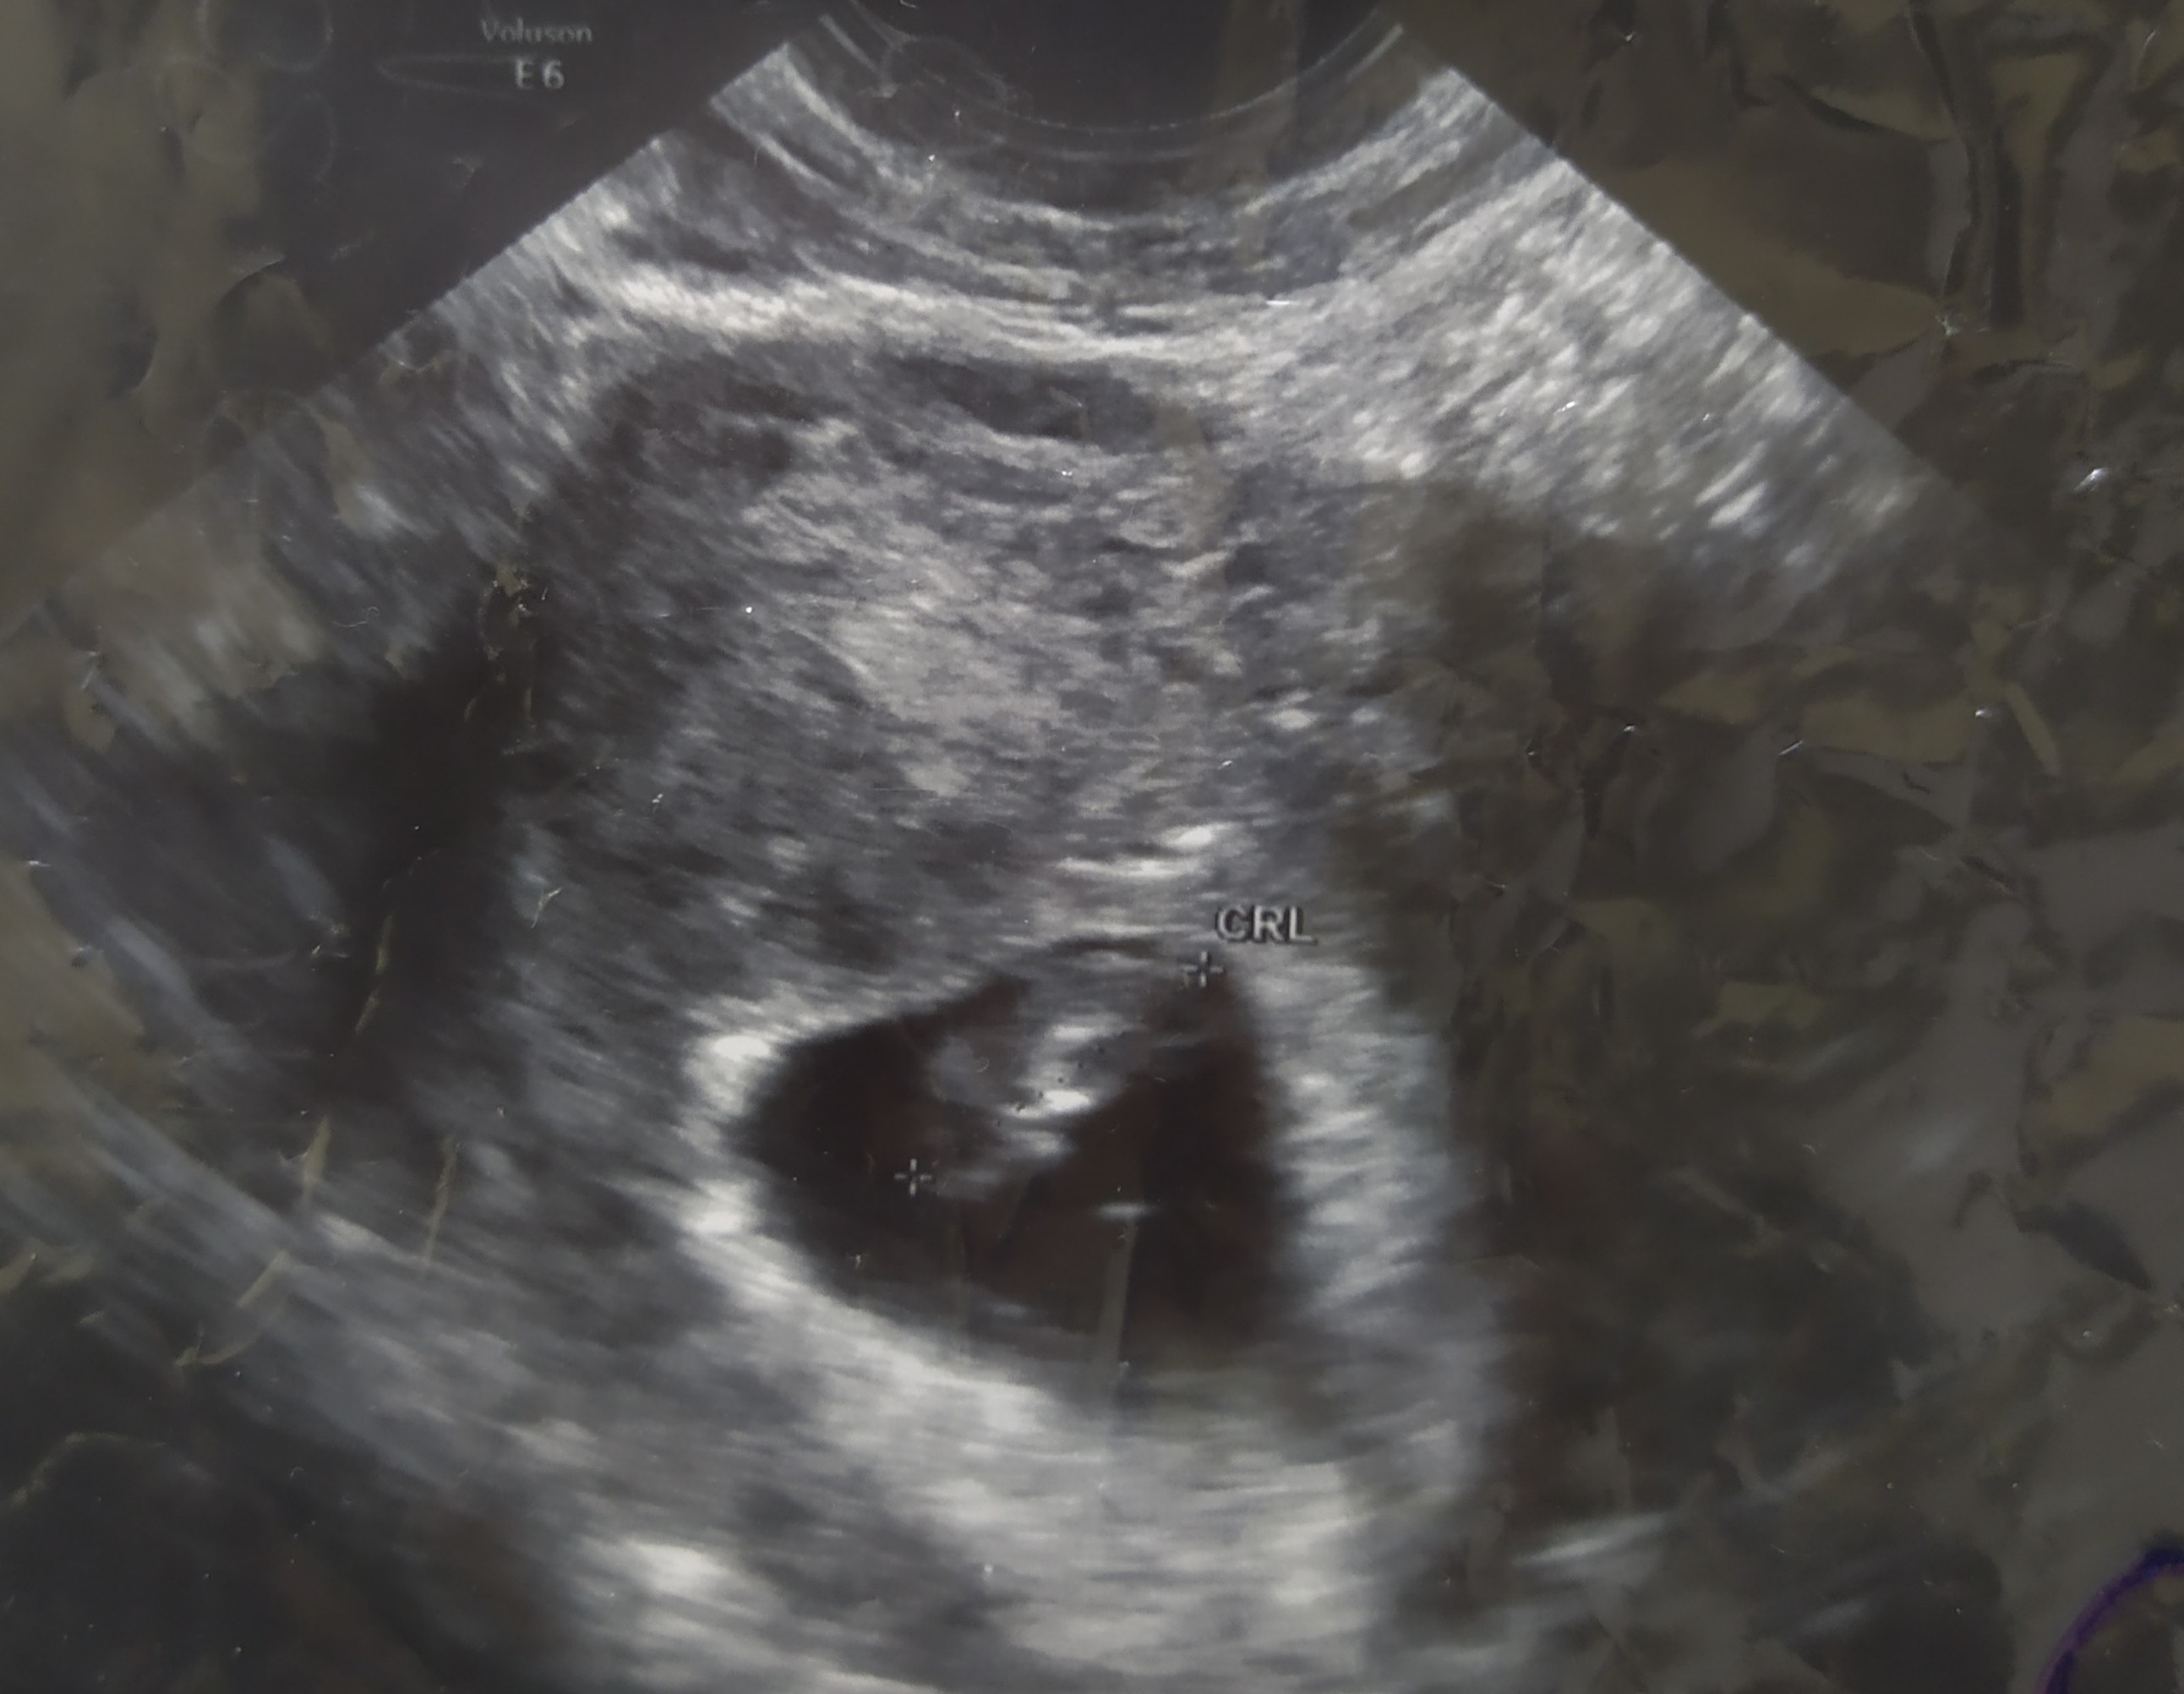

Obecnie w 7 tygodniu ciąży wcześniej plamilam więc dostałam dupahaston 2*1 jak przestanę wtedy acard 150 1*1 wzięłam jedną i w nocy przy podcieraniu była taka różowa krew czy możliwe że to po acardzie ?nic mi lekarz o tym nie mówił że coś takiego może być...

• IMG_20201110_145433.jpg

Mówił że tak może być ale póki co zmniejszyć dawkę brać pół i powinno przejść ale dalej brać razem z dupahastonem następna wizyta za dwa tygodnie teraz oby wszystko dobrze się rozwijało